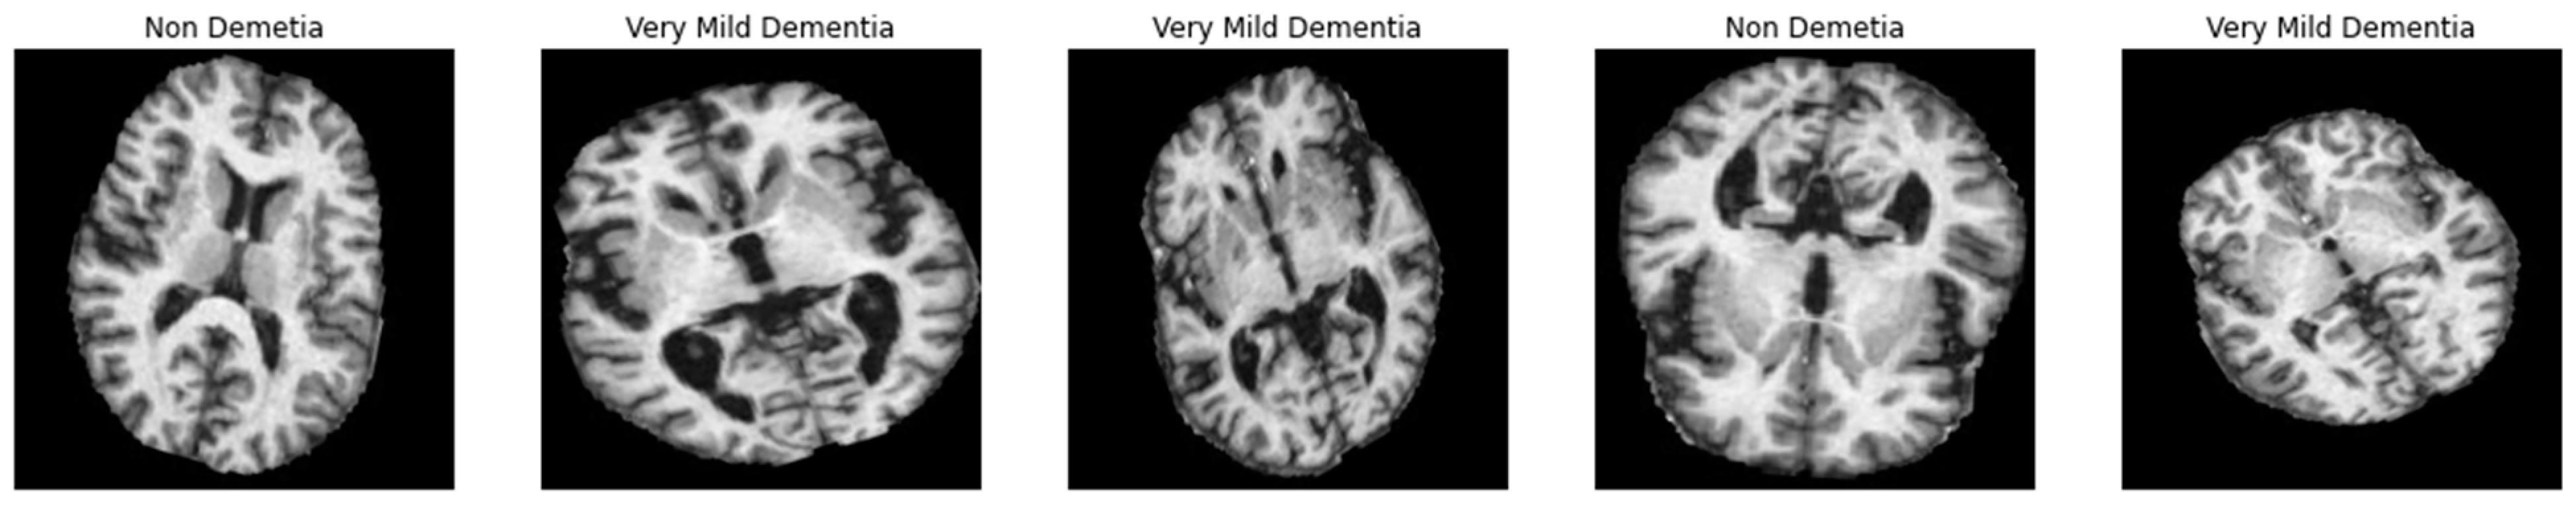

We require enough balanced data to successfully train a DL-based model, as shown in Figure 1a, which shows the bar representation of the class-wise sample distribution of the original dataset. Data balancing is done by purposefully generating the required samples to prevent biased sampling during the DL model’s training. In addition, the imbalanced data may cause the model training to continue favoring classes with many examples. Therefore, to balance our dataset, we used augmentation techniques. The dataset has 5000 total MRI images before data augmentation; after data augmentation, 40,000 MRI images were obtained. As shown in Figure 1, the data is imbalanced. The augmentation strategy and parameters are shown in Table 2. A visual example of the proposed data augmentation approach is shown in Figure 3.

Figure 3.

A visual example of the data augmentation technique applied to MRI image.